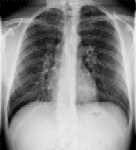

Συγκρίνετε το αποτέλεσμα ρύθμισης φωτεινότητας και ρύθμισης φωτεινότητας πολλαπλών κλιμάκων σε μια εικόνα θώρακα CR:

Μια εικόνα με αυξημένη αντίθεση που χρησιμοποιεί ρύθμιση φωτεινότητας πολλαπλών κλιμάκων δεν εμφανίζει αποκοπή